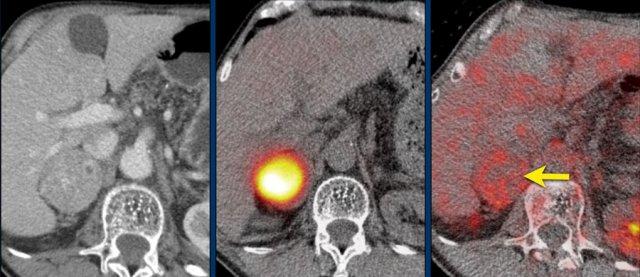

CT thì động mạch và thì tĩnh mạch mặt cắt ngang cho thấy một u tình cờ tuyến thượng thận trái tăng sinh mạch máu.

Metanephrine tự do trong huyết tương tăng cao, có giá trị chẩn đoán u tủy thượng thận (pheochromocytoma).

Phân giai đoạn tiếp theo bao gồm SPECT MIBG và PET-CT FDG, cả hai đều cho thấy sự hấp thu mạnh tại khối u tuyến thượng thận trái, nhưng không có bằng chứng bệnh di căn.